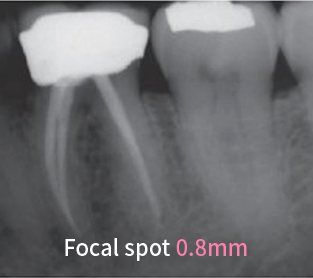

0.4㎜'s Focal Spot gives very clear image to the dentists